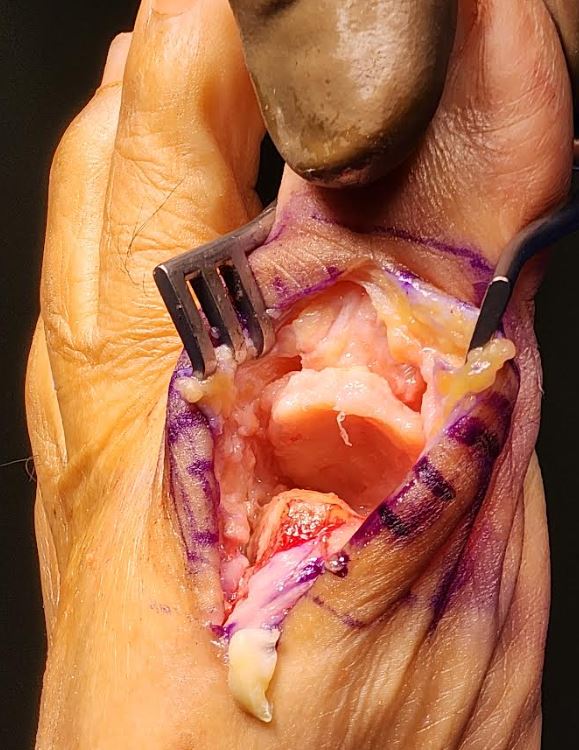

The most common type of arthritis that affects the feet and ankles is osteoarthritis. Osteoarthritis occurs due to general wear-and-tear. It causes cartilage –– a soft, cushion like substance that pads your joints –– to break down. As the cartilage wears away, your bones rub against one another, resulting in pain and mobility issues.

Hallux rigidus (arthritic great toe joint)

Hallux rigidus repair using the Regnauld technique, no metal or foreign body rejection. Immediate weight bearing and range of motion

Arthritic Joint Repair